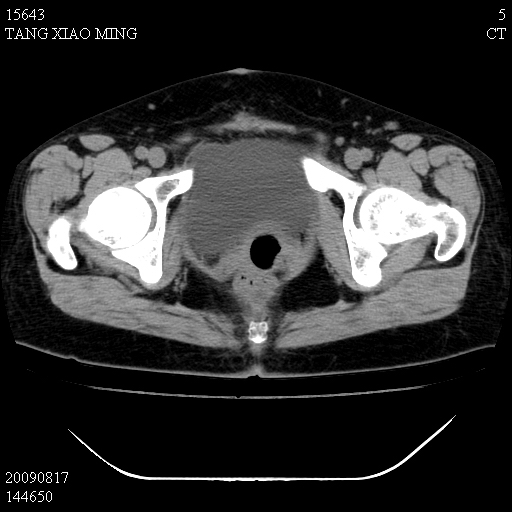

标题: CT21692:盆腔病变

女,33岁,右下腹痛2年余,既往宫外孕病史,如在我院手术,结果下周公布,

可能的诊断。1子宫内膜异位【子宫腺肌症并右卵巢巧克力囊肿】;2 右卵巢囊腺瘤。子宫肌瘤

1)考虑卵巢巧克力囊肿,不排除卵巢囊腺瘤。2)子宫肌瘤可能。

卵巢囊腺瘤,子宫肌瘤,直肠壁厚,不除外占位.